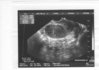

Szczęśliwa:):)